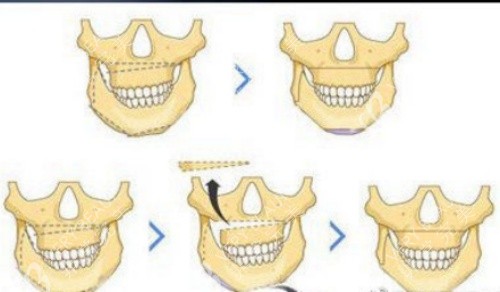

"25岁再来?那得做好'大修'的准备!"广州某口腔专科医院副院长陈明,指着电脑上的3D模拟图说。30岁的张女士就是典型——18岁时怕疼没做,现在下颌骨已经定型,手术得截骨、移位、固定,相当于给房子"拆梁换柱"。

骨骼定型后手术难度翻倍

成年后颌骨像块"老砖头",切割时容易崩裂。陈院长做过对比:18岁前手术,出血量平均80ml;25岁后手术,出血量飙到150ml,术后肿胀时间也延长3-5天。

骨骼可塑性强

这个年龄段的上颌骨像"橡皮泥",医生轻轻一推就能归位;下颌骨像"软陶",容易塑形。王医生做过统计:黄金期手术的患者,90%术后3个月就能正常咀嚼,而成年患者得半年。

王芳医生给他的方案是"上颌前徙术":从口腔内切个小口,把上颌骨整体前移3mm。手术用了2小时,出血量不到50ml。术后第5天,小凯就能吃面条;***0天,他已经敢对着镜子咧嘴笑了。